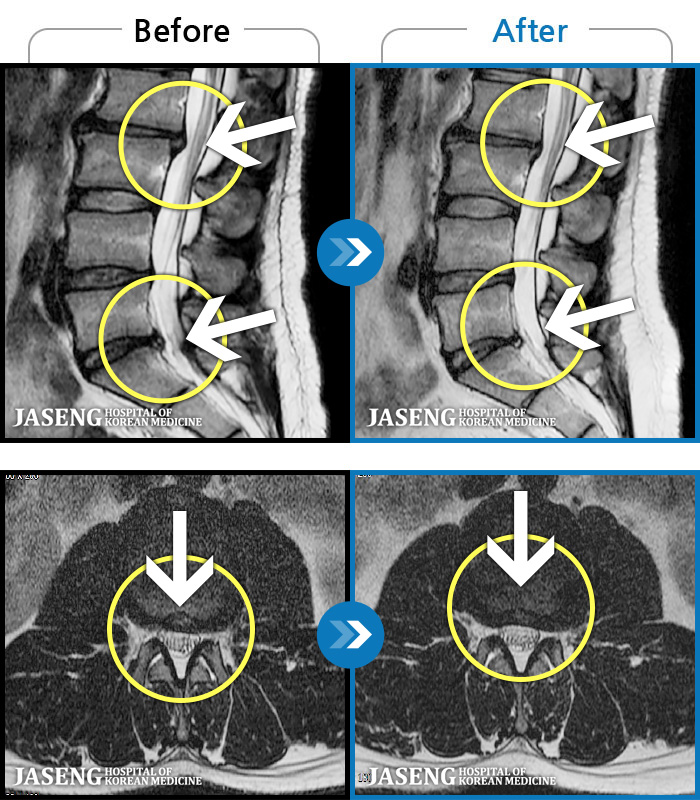

- MRI ġ

MRI ġ

1,304 MRI ũ ʸ Ȯϼ.